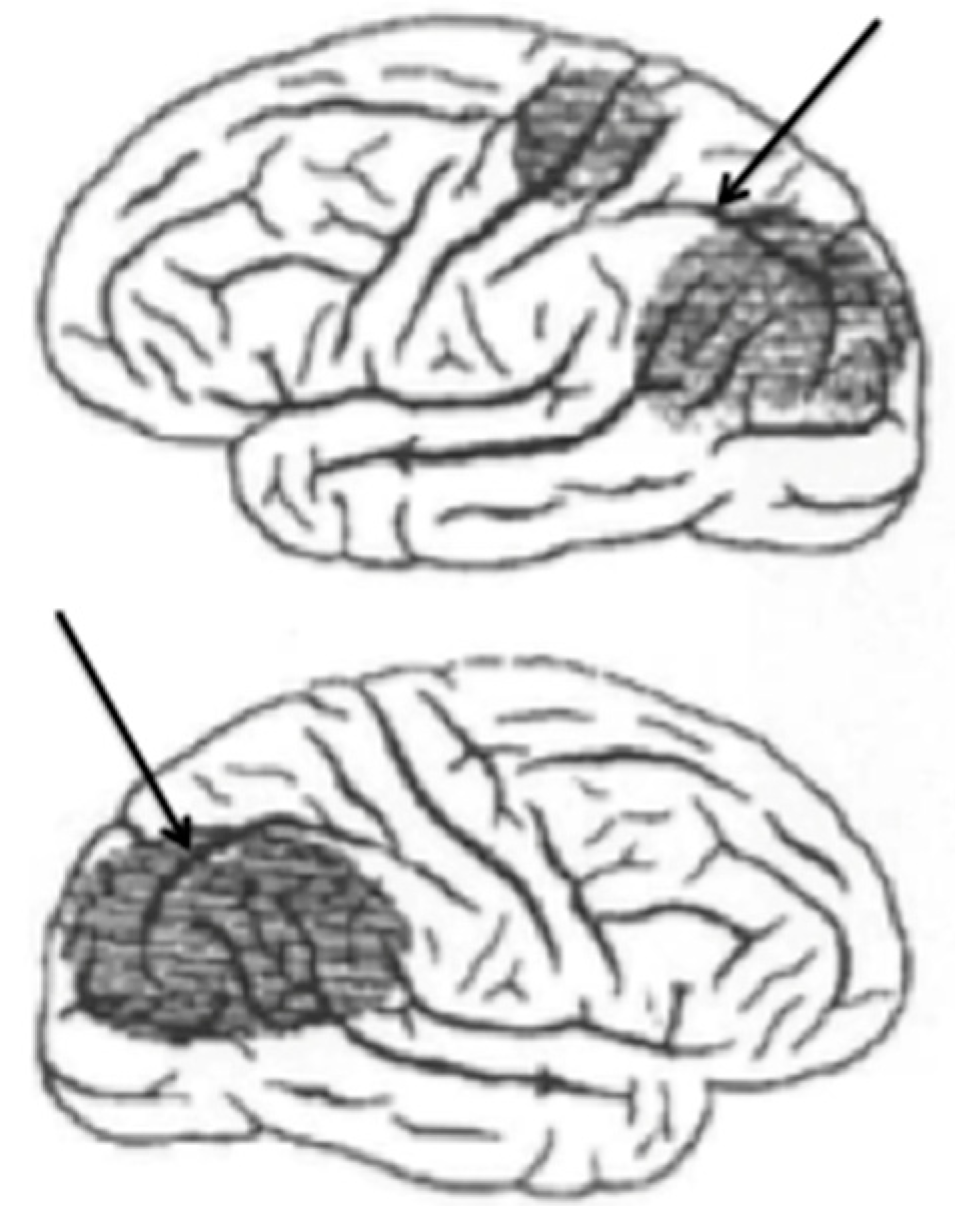

Figure 1 shows an adaptation of a drawing published by Rezso Bálint (1909) showing the regions of both parietal lobes damaged in a patient manifesting a syndrome bearing his name (Husain and Stein 1988). These strokes had damaged the dorsal visual stream bilaterally. Arrows have been added to show the intraparietal sulcus that divides the parietal lobe into the inferior and superior lobules.